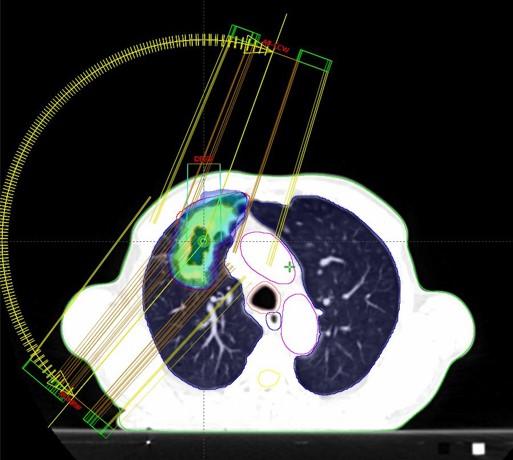

Pluća

Bolesnica, rođena 1958. Dijagnoza: Adenocarcinoma lobi inferioris pulmonis sinistri